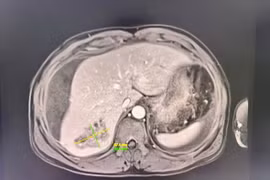

Bụng chướng căng người bệnh nguy kịch do áp xe gan vỡ chảy máu ổ bụng

Ổ áp xe gan vỡ kích thước 57,6mm x 40,6mm, có nhiều ổ giả phình, nhiều dịch máu và mủ tràn ổ bụng. Sau can thiệp, bệnh nhân ổn định, dấu hiệu sinh tồn tốt.